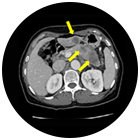

• 췌장암 치료 후  이미지

췌장암 치료 후